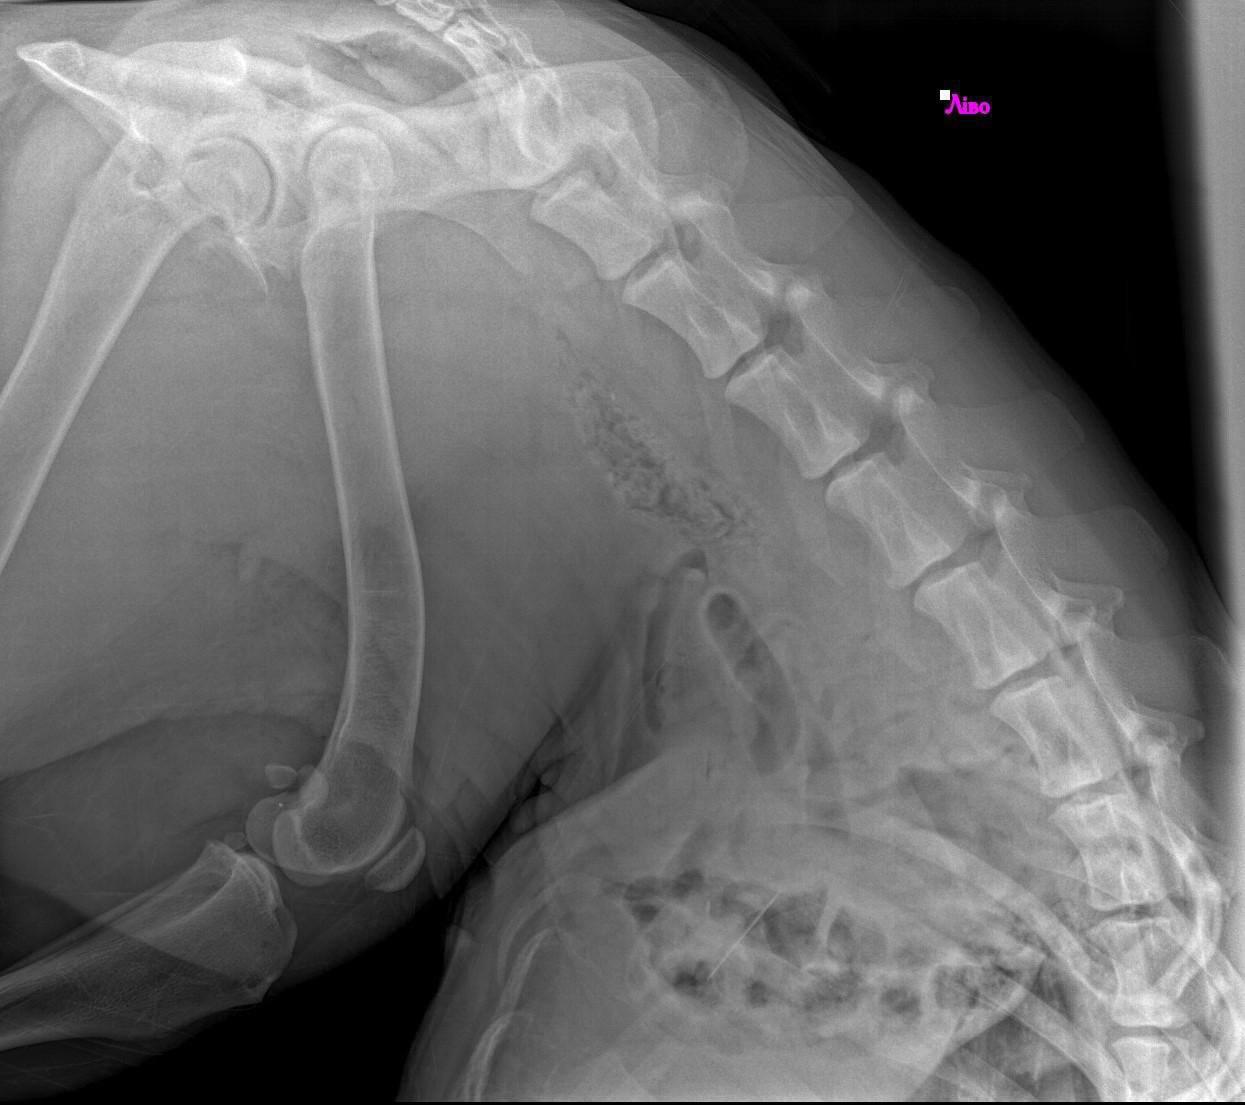

Podczas badań okazało się, że oprócz rany postrzałowej, w jej żołądku tkwi igła.

Kula trafiła na stół operacyjny.

Zespół weterynarzy pracował godzinami, ostrożnie, z nadzieją, że jej ciało wytrzyma kolejną próbę.